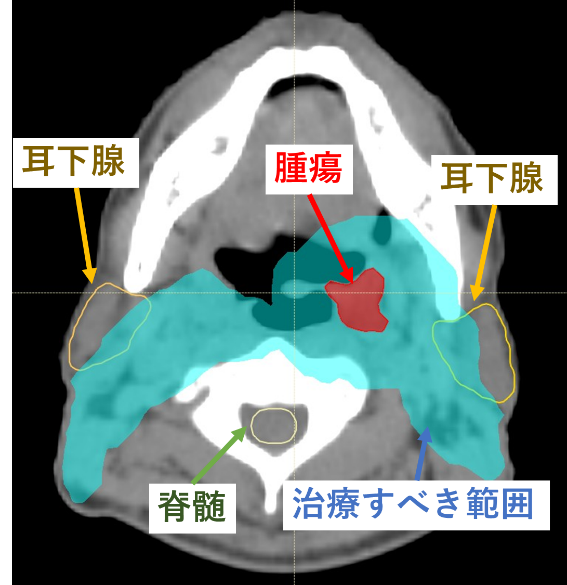

頭頸部癌に対して放射線治療を行った治療計画の一例です。

実際の腫瘍および予防的なリンパ節の範囲が治療として放射線を集中したい部分です。一方で、耳下腺や脊髄などの正常臓器はできるだけ放射線を当てたくない部分です。